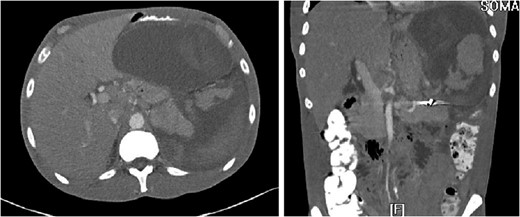

The ‘Islands’ of preserved spleen lit up with IV contrast surrounded by a large collection of old blood and devitalized tissue.

Our patient was vaccinated given that post-procedure CT showed the spleen to be partially necrotic with only two islands of well-perfused, preserved spleen depicting >15% decrease in splenic volume. The plan was to perform interval splenectomy however he was lost to follow up.